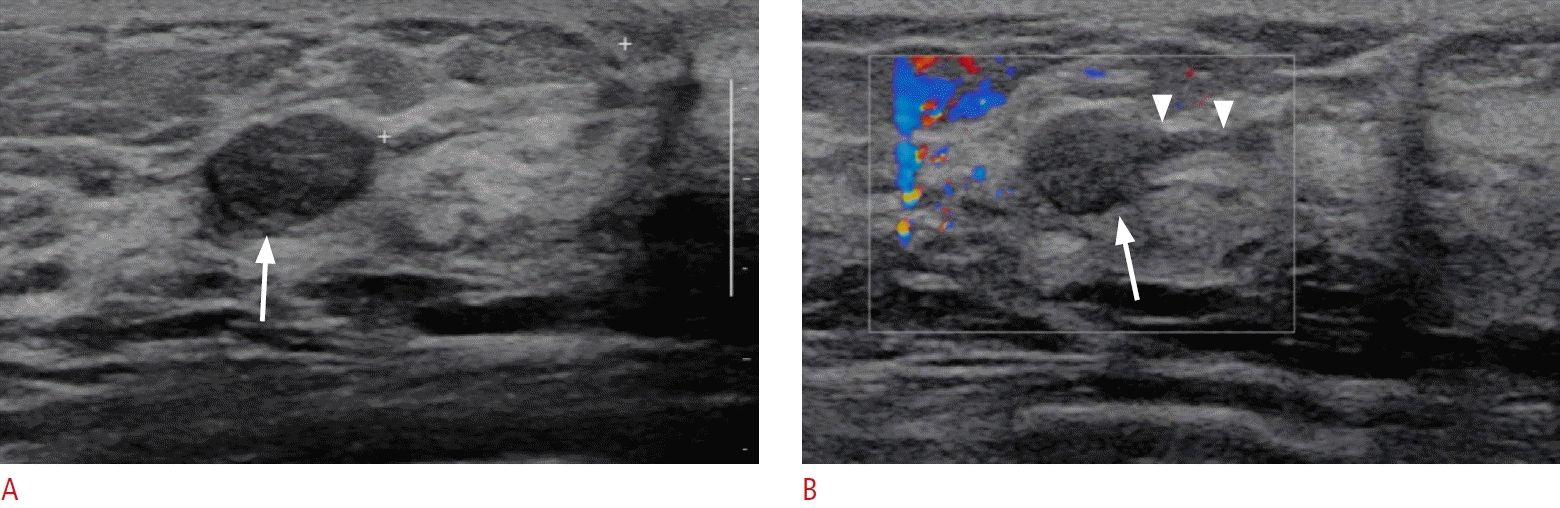

32. Okuno T, Watanabe T, Yamaguchi T, Konno S, Takaki R, Watanabe R, et al. Usefulness of color Doppler and strain elastography adjunctive to B-mode ultrasonography in the diagnosis of nonmass abnormalities of the breast: results of the BC-07 multicenter study of 385 cases. J Med Ultrason (2001). 2025; 52:157–168.